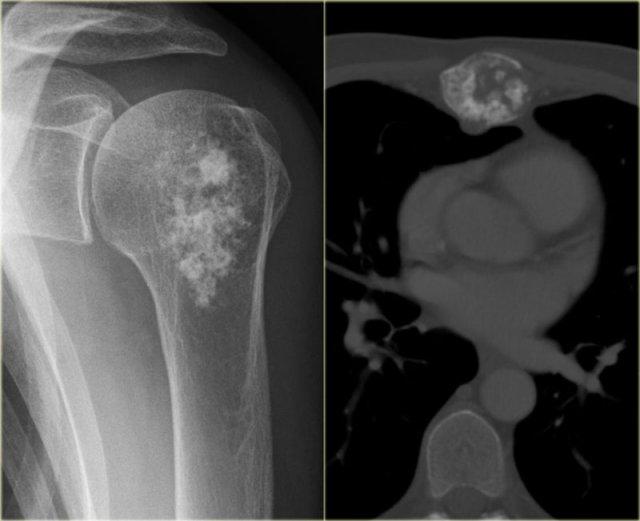

Đây là hai tổn thương khác ở các bệnh nhân khác nhau được chứng minh là u sụn ác tính (chondrosarcoma).

Tổn thương xơ cứng ở chỏm xương cánh tay hoàn toàn có thể là u sụn lành tính (enchondroma) dựa trên các đặc điểm hình ảnh.

Thông thường không có triệu chứng, tuy nhiên, ở bệnh nhân trưởng thành có tổn thương sụn ở xương dài, đặc biệt khi kích thước lớn hơn, cần luôn cân nhắc đến u sụn ác tính độ thấp (low-grade chondrosarcoma).

Hình ảnh X-quang thường và ảnh MRI chuỗi xung T1 có tiêm thuốc tương phản với kỹ thuật xóa mỡ theo mặt phẳng coronal của tổn thương vừa tiêu xương vừa đặc xương ở thân xương đùi đoạn xa.

Lưu ý sự dày lên đồng nhất của vỏ xương.

Không có vôi hóa.

Hình ảnh MRI cho thấy tổn thương có bờ múi và ngấm thuốc dạng nốt.

Sự ngấm thuốc đồng nhất ở phần trên kèm theo phù nề và dày vỏ xương không điển hình cho u sụn ác tính độ thấp.

U sụn ác tính độ cao cần được xem xét trong chẩn đoán phân biệt.

Biopsy revealed dedifferentiated chondrosarcoma.